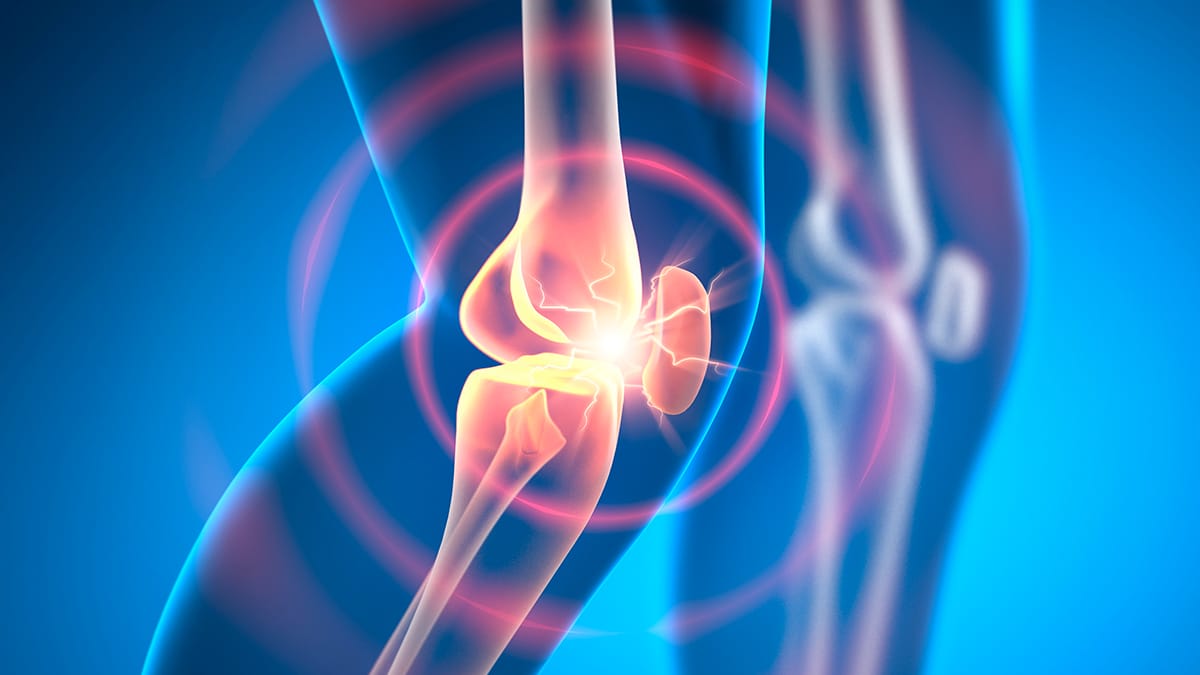

Nova droga experimental pode reverter a osteoartrite em semanas, aponta pesquisa com animais

Pesquisadores da Universidade do Colorado desenvolveram uma nova terapia que promete reverter a osteoartrite em apenas algumas semanas. A condição, que afeta milhões de pessoas em todo o mundo, causa dor e degradação das articulações. A nova abordagem envolve a injeção de um sistema de liberação lenta de medicamentos diretamente na articulação danificada.

Os experimentos com animais demonstraram que a injeção do novo tratamento pode estimular as células de cartilagem e os ossos do próprio corpo a realizar reparos eficazes. A equipe de pesquisa, liderada pela engenheira química Stephanie Bryant, conseguiu avançar rapidamente, passando de uma ideia inicial para a demonstração de resultados positivos em dois anos. A pesquisa ainda não foi revisada por pares, mas os resultados preliminares são promissores.

A nova terapia utiliza um sistema de entrega de medicamentos que se instala na articulação e recruta células do corpo para reparar as lacunas na cartilagem. Além disso, a equipe está desenvolvendo um implante injetável que se fixa no local e ajuda na regeneração do tecido. Essa abordagem visa não apenas tratar a dor, mas também restaurar a função articular, oferecendo uma alternativa às cirurgias invasivas.

O tratamento está atualmente na fase inicial de testes em animais, com planos para avançar para a fase dois, que avaliará a segurança e a toxicologia do procedimento. A equipe espera iniciar ensaios clínicos em humanos dentro de 18 meses, dependendo dos resultados das próximas etapas de pesquisa. A osteoartrite apresenta quatro estágios, e a terapia está sendo desenvolvida para atender a diferentes níveis da condição.

Os avanços na pesquisa sobre osteoartrite indicam um futuro promissor para o tratamento da doença. A nova terapia, que utiliza o próprio corpo para reparar articulações danificadas, pode transformar a abordagem atual, que se limita a gerenciar a dor ou realizar cirurgias. A continuidade dos estudos e o sucesso nas fases de testes são fundamentais para que essas inovações se tornem uma realidade clínica.